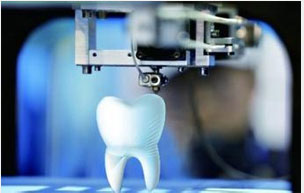

3D导航模拟种植技术

精准:采用意大利NewTom锥形束CBCT,可提供关于植入区骨(高度、厚度、宽度、骨密度)、,确保种植的位置、角度、深度与模拟效果分毫不差,建立咬合关系。

快速:种植手术整个周期由传统的6个月缩短为2个月左右,如果配合德国威兰德CAD/CAM“即刻种植,即刻负载”技术,顾客种完牙的当天就可以正常饮食。

微创:丹麦3shape3D设计系统,进行种植方案完美模拟,并打印出种植导板,医生在术前设计就能轻易地避开重要神经和血管,无需手术切口便可精准植入种植体,出血很少,把种植风险和损伤大大降低。

3D导航模拟种植技术